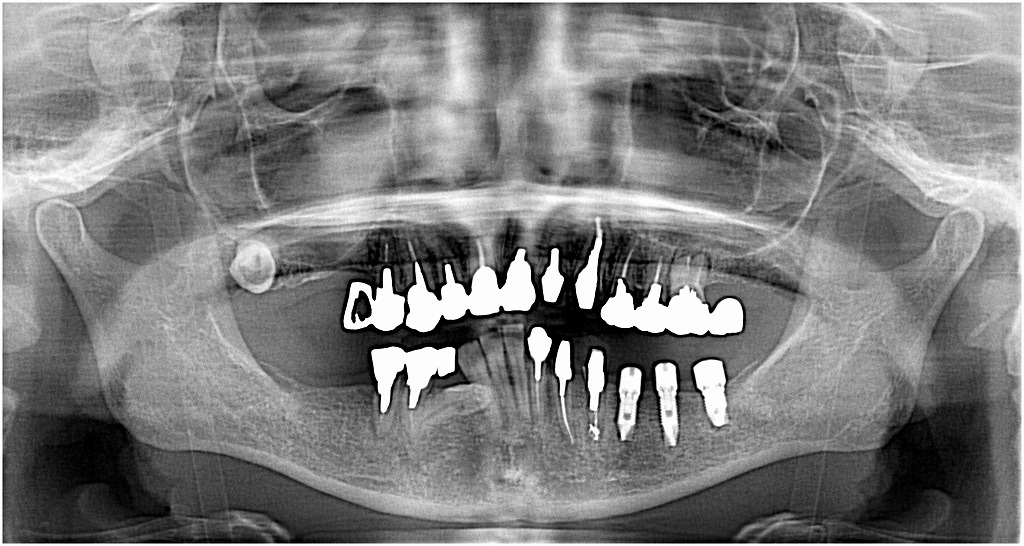

左下の奥の欠損部へインプラントを3本埋入していきます |お知らせ |広島市安佐南区の歯科医院 左下の奥の欠損部へインプラントを3本埋入していきます トップ お知らせ・ブログ お知らせ 左下の奥の欠損部へインプラントを3本埋入していきます 左下の奥の欠損部へインプラントを3本埋入していきます 術前のパノラマになります 左下の4番部の歯が割れました インプラント埋入時になります 綺麗に入りました 縫合して終了となります 術後のパノラマになります 1週間後になります Web診療予約 初めての方へ 選ばれ続ける理由 院内設備について 歯が痛いしみる一般歯科 歯がぐらぐらする歯周病 健康な歯を保ちたい予防歯科 子供の虫歯予防をしたい小児歯科 銀歯をセラミックに審美歯科 白い歯を目指しませんか?ホワイトニング 矯正専門医がいるので安心矯正歯科 抜けた歯を補いたいインプラント・入れ歯 医院案内 スタッフ紹介 メリィハウス歯科クリニックオフィシャルホームページ ラベンダー歯科クリニックオフィシャルホームページ お知らせ・ブログ ホーム 診療科目 一般歯科 歯周病治療 予防治療 小児歯科 審美治療 ホワイトニング 矯正歯科 入れ歯・インプラント マウスピース矯正 初めての方へ 院長・スタッフ 設備紹介 医院案内・アクセス メニューを閉じる